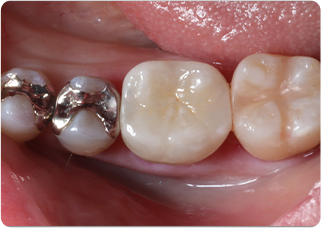

精密根管治療②

術前

術後

| 主訴 | 奥歯で噛むと痛い |

|---|---|

| 治療期間/回数 | 1ヵ月、3回 |

| 価格(税込) | 88,000円(税込) |

| リスク・副作用 | 病変再発、歯根破折の可能性 |

| ポイント | う蝕検知液を用い、むし歯の取り残しが無いようにし、ラバーダム防湿を行い、無菌的に根管治療を行った。根管充填材は、殺菌作用の強い保険適応外のMTAセメントを使用した。 |